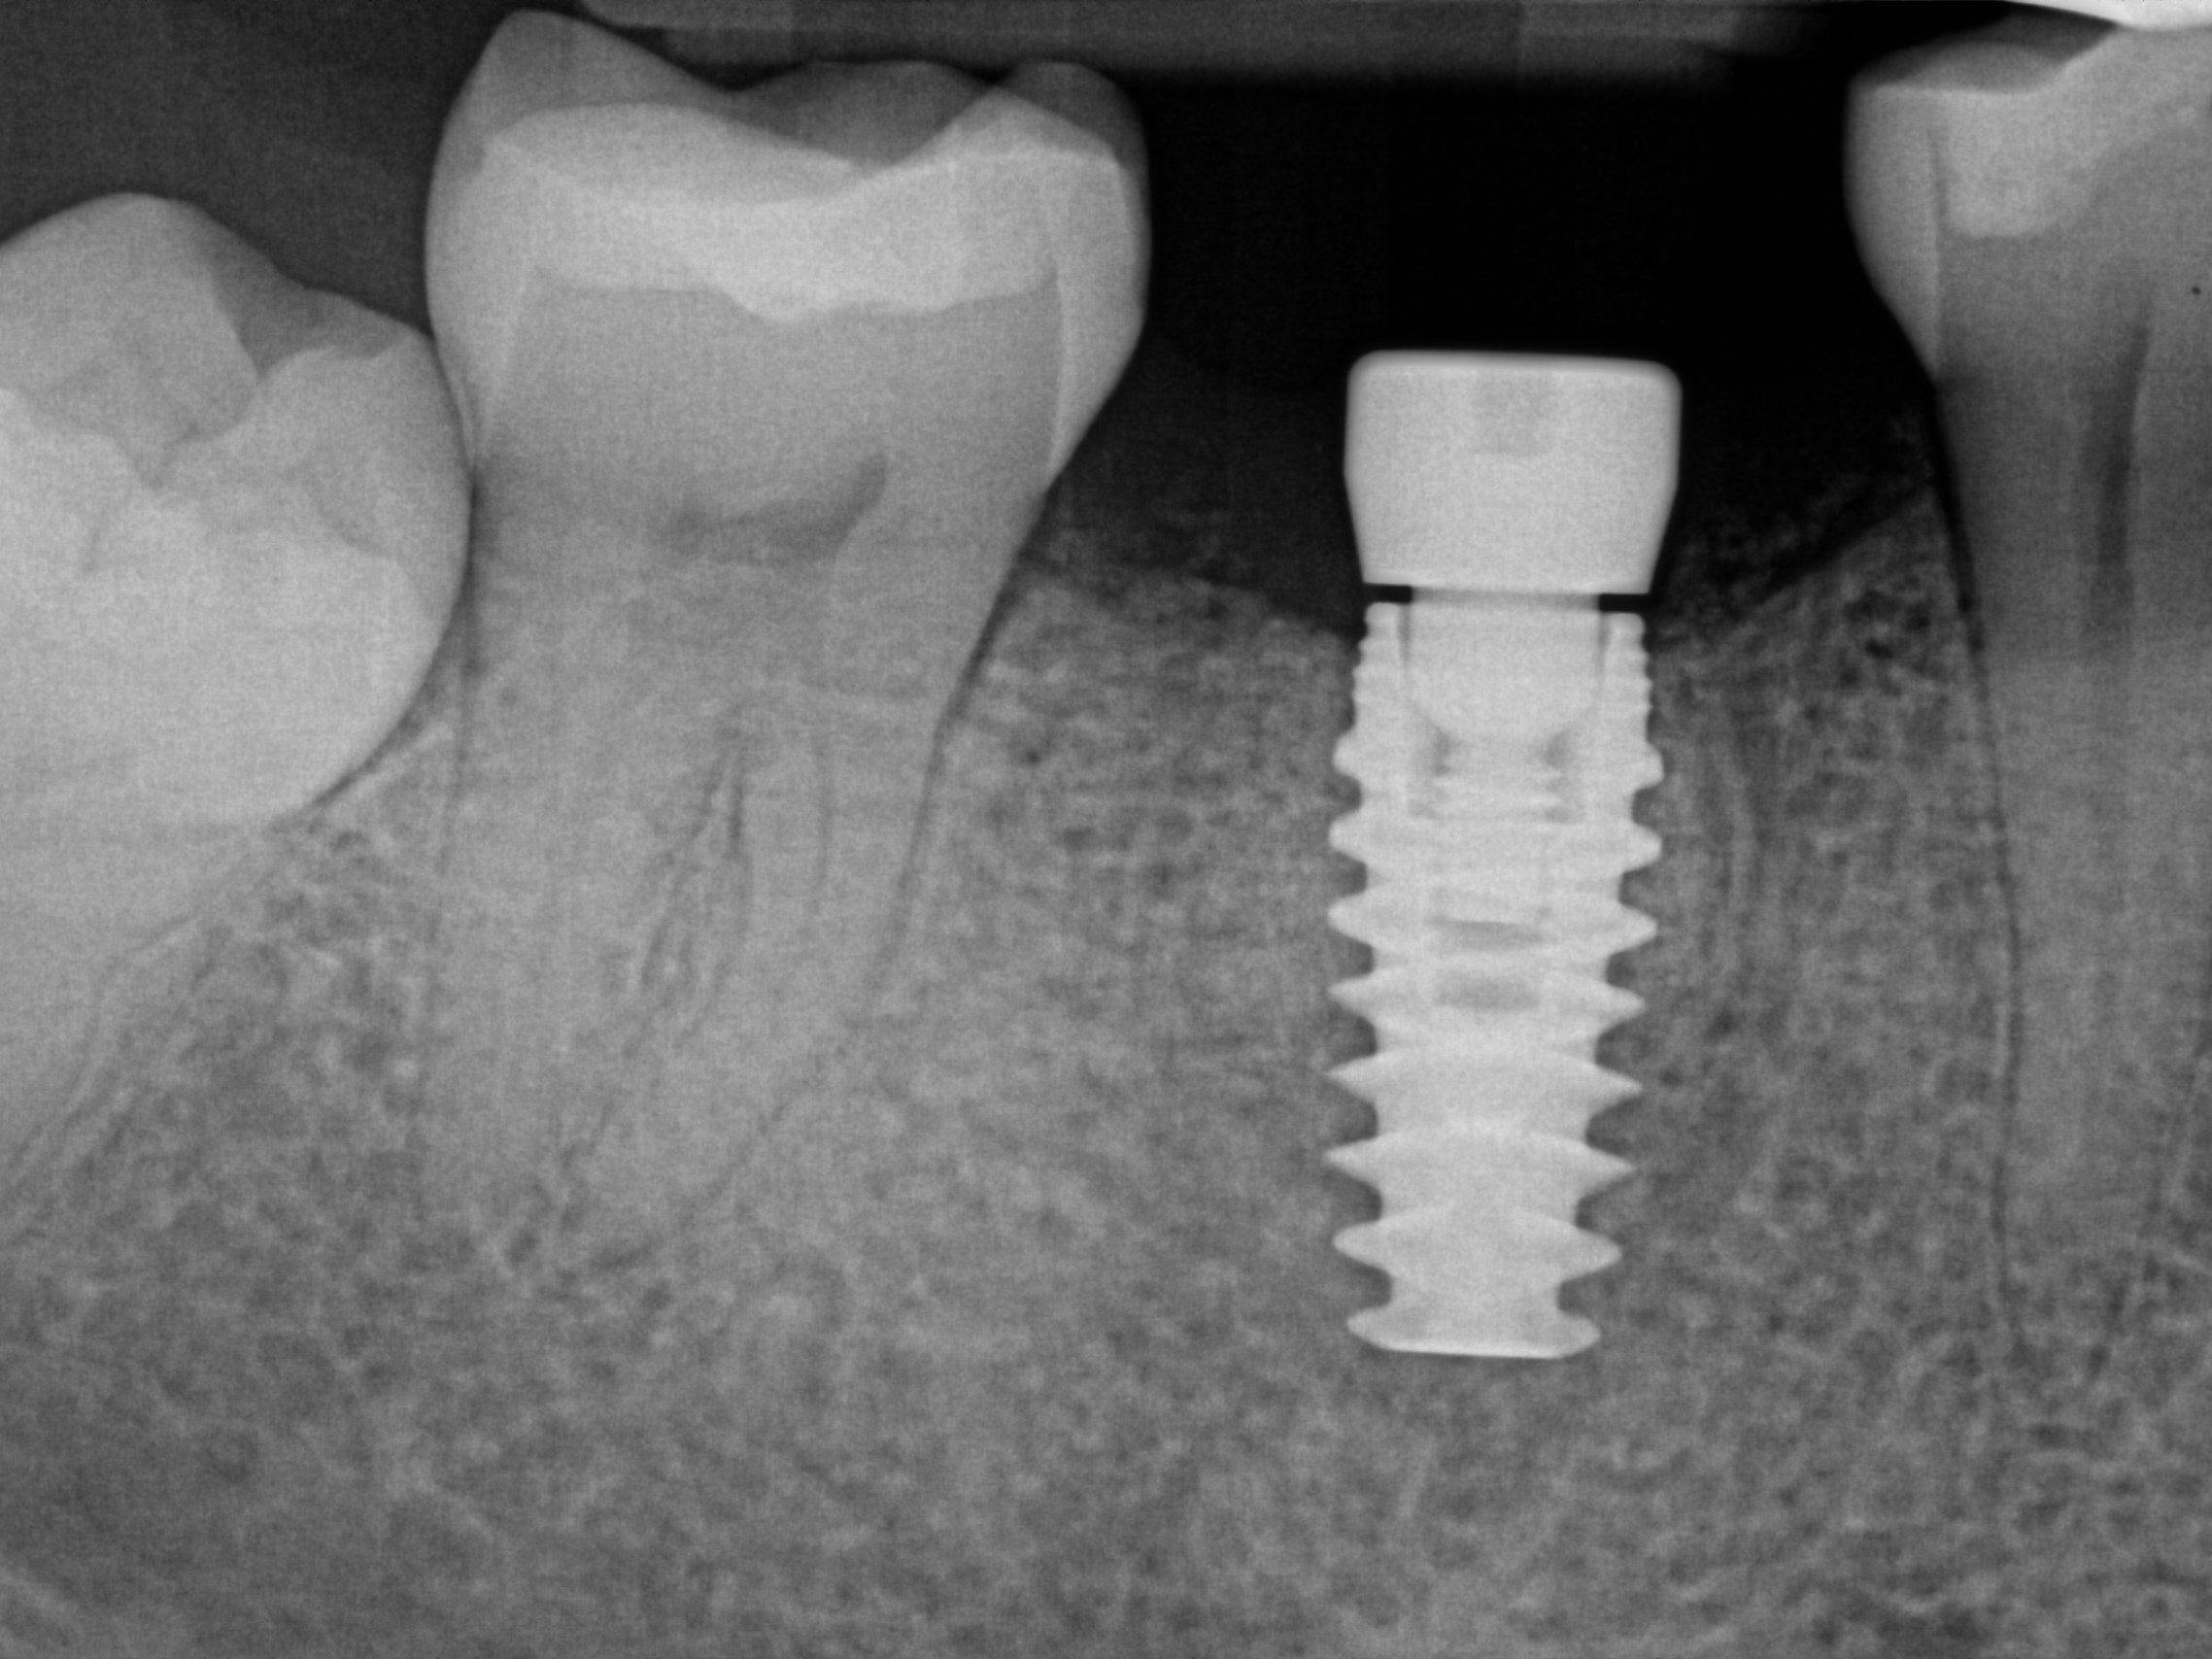

Custom Implant Crown